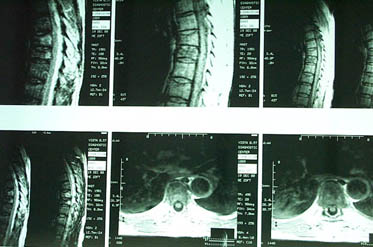

Уважаемые участники форума, Больной 53 лет, с жалобами на выраженные боли в области грудного отдела позвоночника, чувство онемения и стягивания в правой кисти, боли в мышцах конечностей и туловища. Отмечается парез правой верхней конечности.

В декабре 99 года перенес геморрагический а потом и ишемический инсульт левой задне-лобно-височной области. Выписался со значителсным улучшением неврологической симптоматики. Через год, на фоне обычного самочувствия, пожаловался на боль в спине, после чего появилось тоническое напряжение правой руки, половины туловища, перерастающее в приступ с судорогами по типутонико-клонических и потерей сознания. Госпитализирован. На CТ выявлен большой очаг в виде кистозной полости. Компрессионный перелом 8-9 грудных позвонков. В последующем, на протяжении полутора лет в общей сложности отмечено 5 аналогичных по формуле припадков. Падения с высоты во время приступов небыло. Также отрицает травмы позвоночника в анамнезе. ПовторнаяR-графия и СТ позвоночника выявила патологический компрессионный перелом и остеопороз тел Th 6; 7; 8; 9, (отрицательная динамика). Наличиенеобластомного процесса не выявлено. Все анализы, включая паратгормон, впределах нормы кроме:Са-Т - 2.66 (от 2.02 до 2.60)Р - 1.72 (от 081 до 1.62)СОЭ - 34мм/часСнимки 1, 2, 3, 4 прилагаются.Возникает ряд вопросиов: Может ли деструкция в левой задне-лобно-височной области быть связана с системним остеопорозм позвонков и пат. переломом? Моигут ли эпилптические приступы явиться причиной компрессионного переломапозвонков? Какие дополнительные исследования нужны для дифдиагностики болезни Куммелля? Тактика лечения (корсет?), показания и противопоказания к хирургическому вмешательству на позвонках в данной ситуации Прогноз?Буду благодарен любым соображениям,Аршак Мирзоян